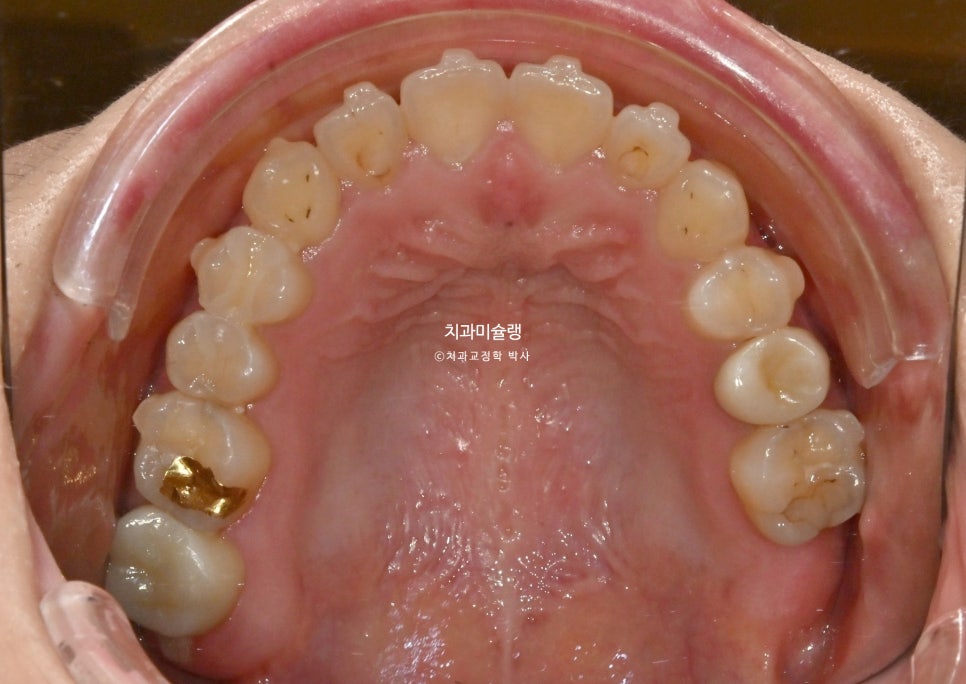

12월부터 2월까지 추가장치 7개를 모두 낀 후 모습입니다.

중심선이 맞아졌으며 송곳니를 포함한 위 6개 앞니 높이가 균일해졌습니다.

치열이 바르고 단차가 없이 높낮이가 균일해야 무삭제라미네이트도 균일한 두께로 제작이 됩니다.

무삭제 라미네이트는 두께가 엷은게 핵심이라 본래 치아색이 어느정도 비쳐 나오기 때문에, 라미네이트 두께가 들쑥날쑥 하면 색깔도 미세하게 얼룩덜룩 해집니다.